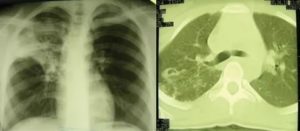

В последствии они трансформируются в отложения солей кальция, которые никак себя не проявляют и диагностируются случайно при прохождении флюорографии или рентгенологического исследования. Как выглядят кальцинаты на рентгеновском снимке показано на фото ниже.

Кальцинаты в легких на рентгене

Сами по себе эти образования не опасны и никак не нарушают функции легких. Однако кальцинаты способствуют снижению местных защитных сил и общей резистентности, поэтому люди с такой патологией более подвержены бронхо-легочным инфекциям. Им рекомендуется регулярно проходить профилактические осмотры и дважды в год делать флюорографию.

Диагностируют эту проблему с помощью рентгена или компьютерной томографии.